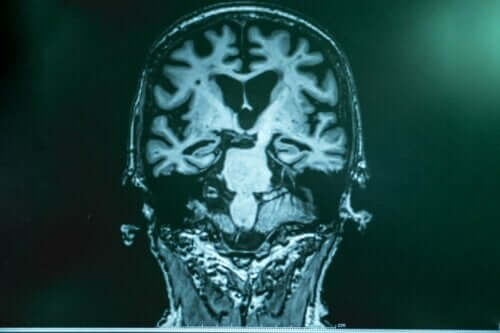

Vet du hva gammabølger er? Er du klar over fordelene med bølgehjernestimulering som en behandling for pasienter med Alzheimers sykdom? Fremskrittet innen vitenskap og teknologi og deres forhold har tillatt utvikling av nye behandlinger som bokstavelig talt er en solstråle for disse pasientene.

Alzheimers sykdom er fortsatt et mysterium. Det er en sykdom der legene fortsatt bare kan bekrefte dødsfall. Opprinnelsen er fortsatt uklar.

Ingen terapi, medikamenter eller andre former for behandling har ennå blitt funnet å bremse eller reversere denne sykdommen. Derfor er enhver liten fremgang som bremser progresjonen eller til og med forbedrer kognisjonen, en stor prestasjon.